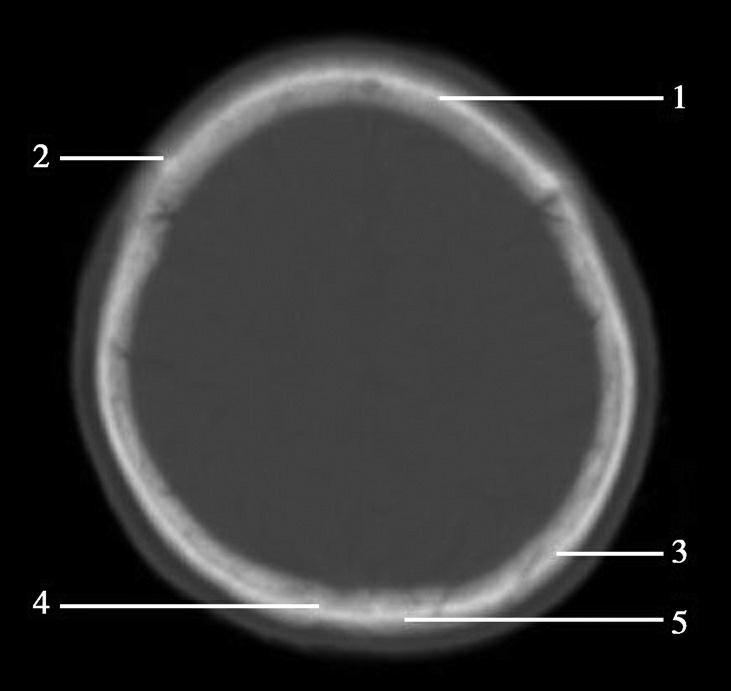

枕骨隆突位于枕部正中间偏下面部分,为一骨性隆突。部分人骨性隆突较为突出,可触及(图1-2-81)。

图1-2-81 枕骨隆突(箭)

脑蛛网膜在硬脑膜构成的上矢状窦附近形成许多绒毛状突起,称为蛛网膜颗粒。蛛网膜颗粒粗大时,可突入硬脑膜窦内,可压迫邻近颅骨内板导致局部骨质吸收等改变(图1-2-82)。

图1-2-82 蛛网膜颗粒(箭)